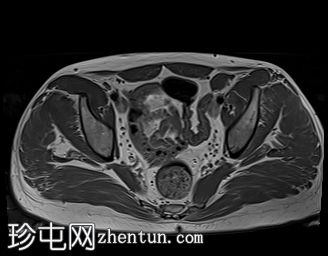

MRI

左侧阴囊空虚。

左侧睾丸位于盆腔左侧前壁,腹股沟管上方。其体积较小(与对侧正常的右侧睾丸相比)。T2加权像呈高信号,T1加权像呈低信号,未见明显局灶

性病

变。

右侧睾丸位于右侧阴囊内,大小和形状正常。